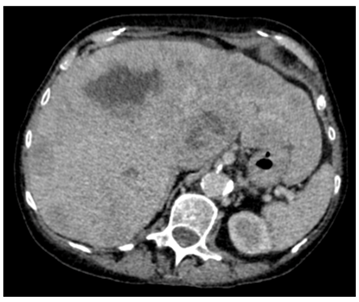

Our patient was a 79-year old female with severe progressive chronic obstructive pulmonary disease (COPD) on home oxygen, type 2 diabetes, hypertension and angina. She presented with type 1 respiratory failure and chest pain in December 2015. A computed tomography pulmonary angiogram (CTPA)4 months prior to this admission, showed no pulmonary embolism but did show a solitary liver lesion (Figure 1), measuring 2.5cm x 2.8cm that was suspicious for metastasis. A subsequent contrast-enhanced staging CT abdomen and pelvis demonstrated multiple liver metastases (Figure 2) with a 5.5cm solid-cystic lesion arising from her left kidney. After discussion with the Hepatobiliary multidisciplinary team (MDT), she underwent a percutaneous biopsy of the liver lesions, which showed metastatic carcinoma of indeterminate primary. She was seen by our Oncologists and was deemed suitable only for palliative treatment at this stage due to a presumed metastatic renal cancer and her multiple co-morbidities.

Figure 1: CTPA showing solitary liver lesion in August 2015.